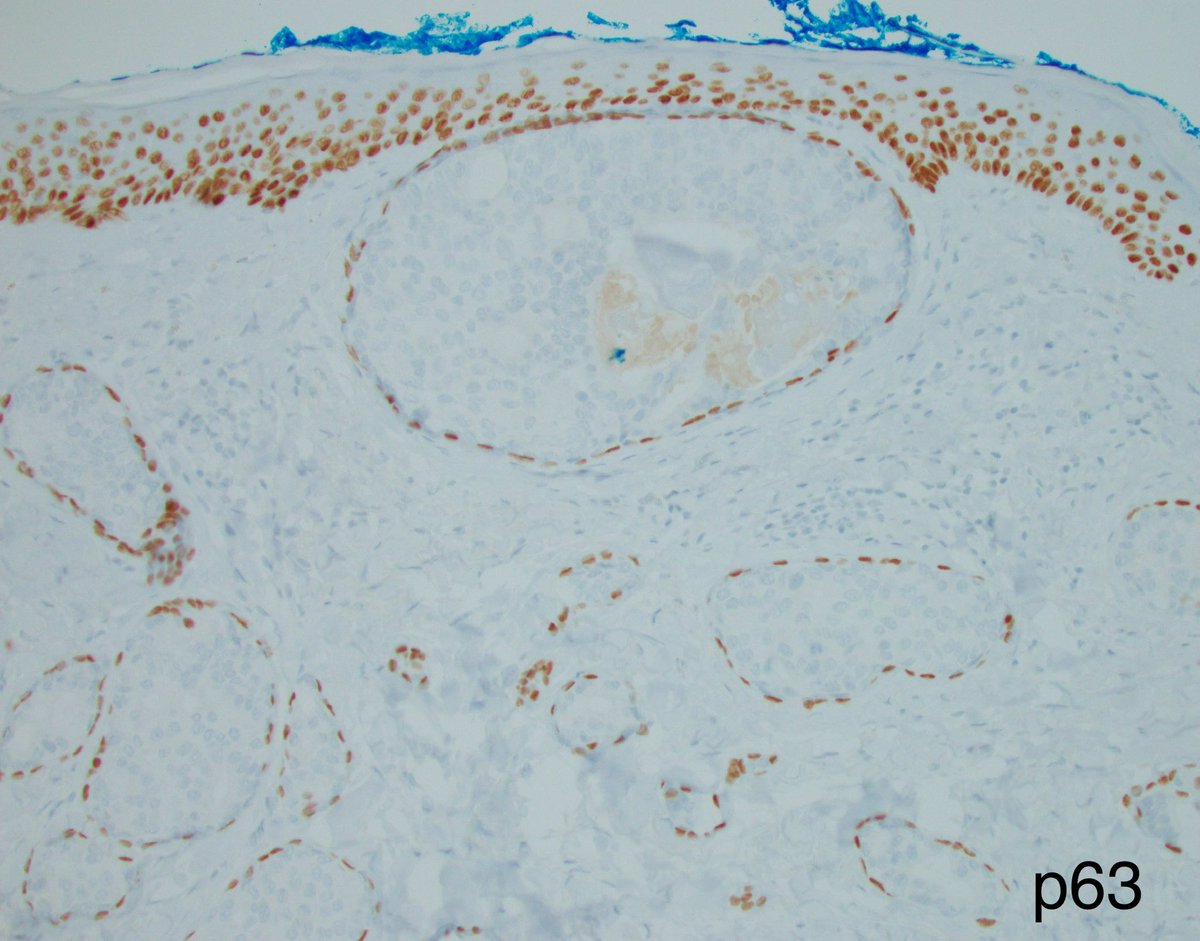

This was a curbside consult from #dermpath. Patient has a history of mastectomy for breast cancer and is now presenting with a chest wall skin nodule. What is your diagnosis? - IHC: p63 @wusm_pathology WashU Medicine Pathology & Immunology Education #breastpath #PathTwitter #PathX